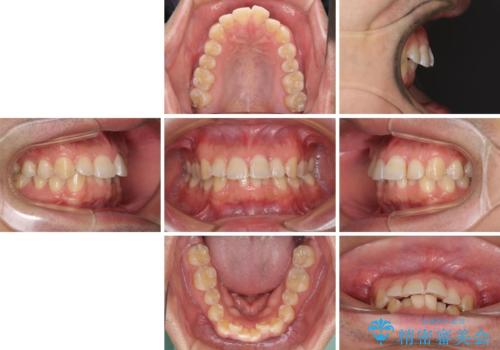

ディープバイトと叢生を解消 インビザライン矯正

- 前歯のデコボコを強い咬みしめを気にして来院された患者様です。

インビザラインを用いて、前歯の叢生を解消するとともに、ディープバイトを改善していくこととしました。

ディープバイトが改善されたことで、顎への負担が軽減され、更には上顎前歯の突出感も改善することができました。

矯正治療後には欠けてしまった修復物をセラミックインレーにて修復治療しました。